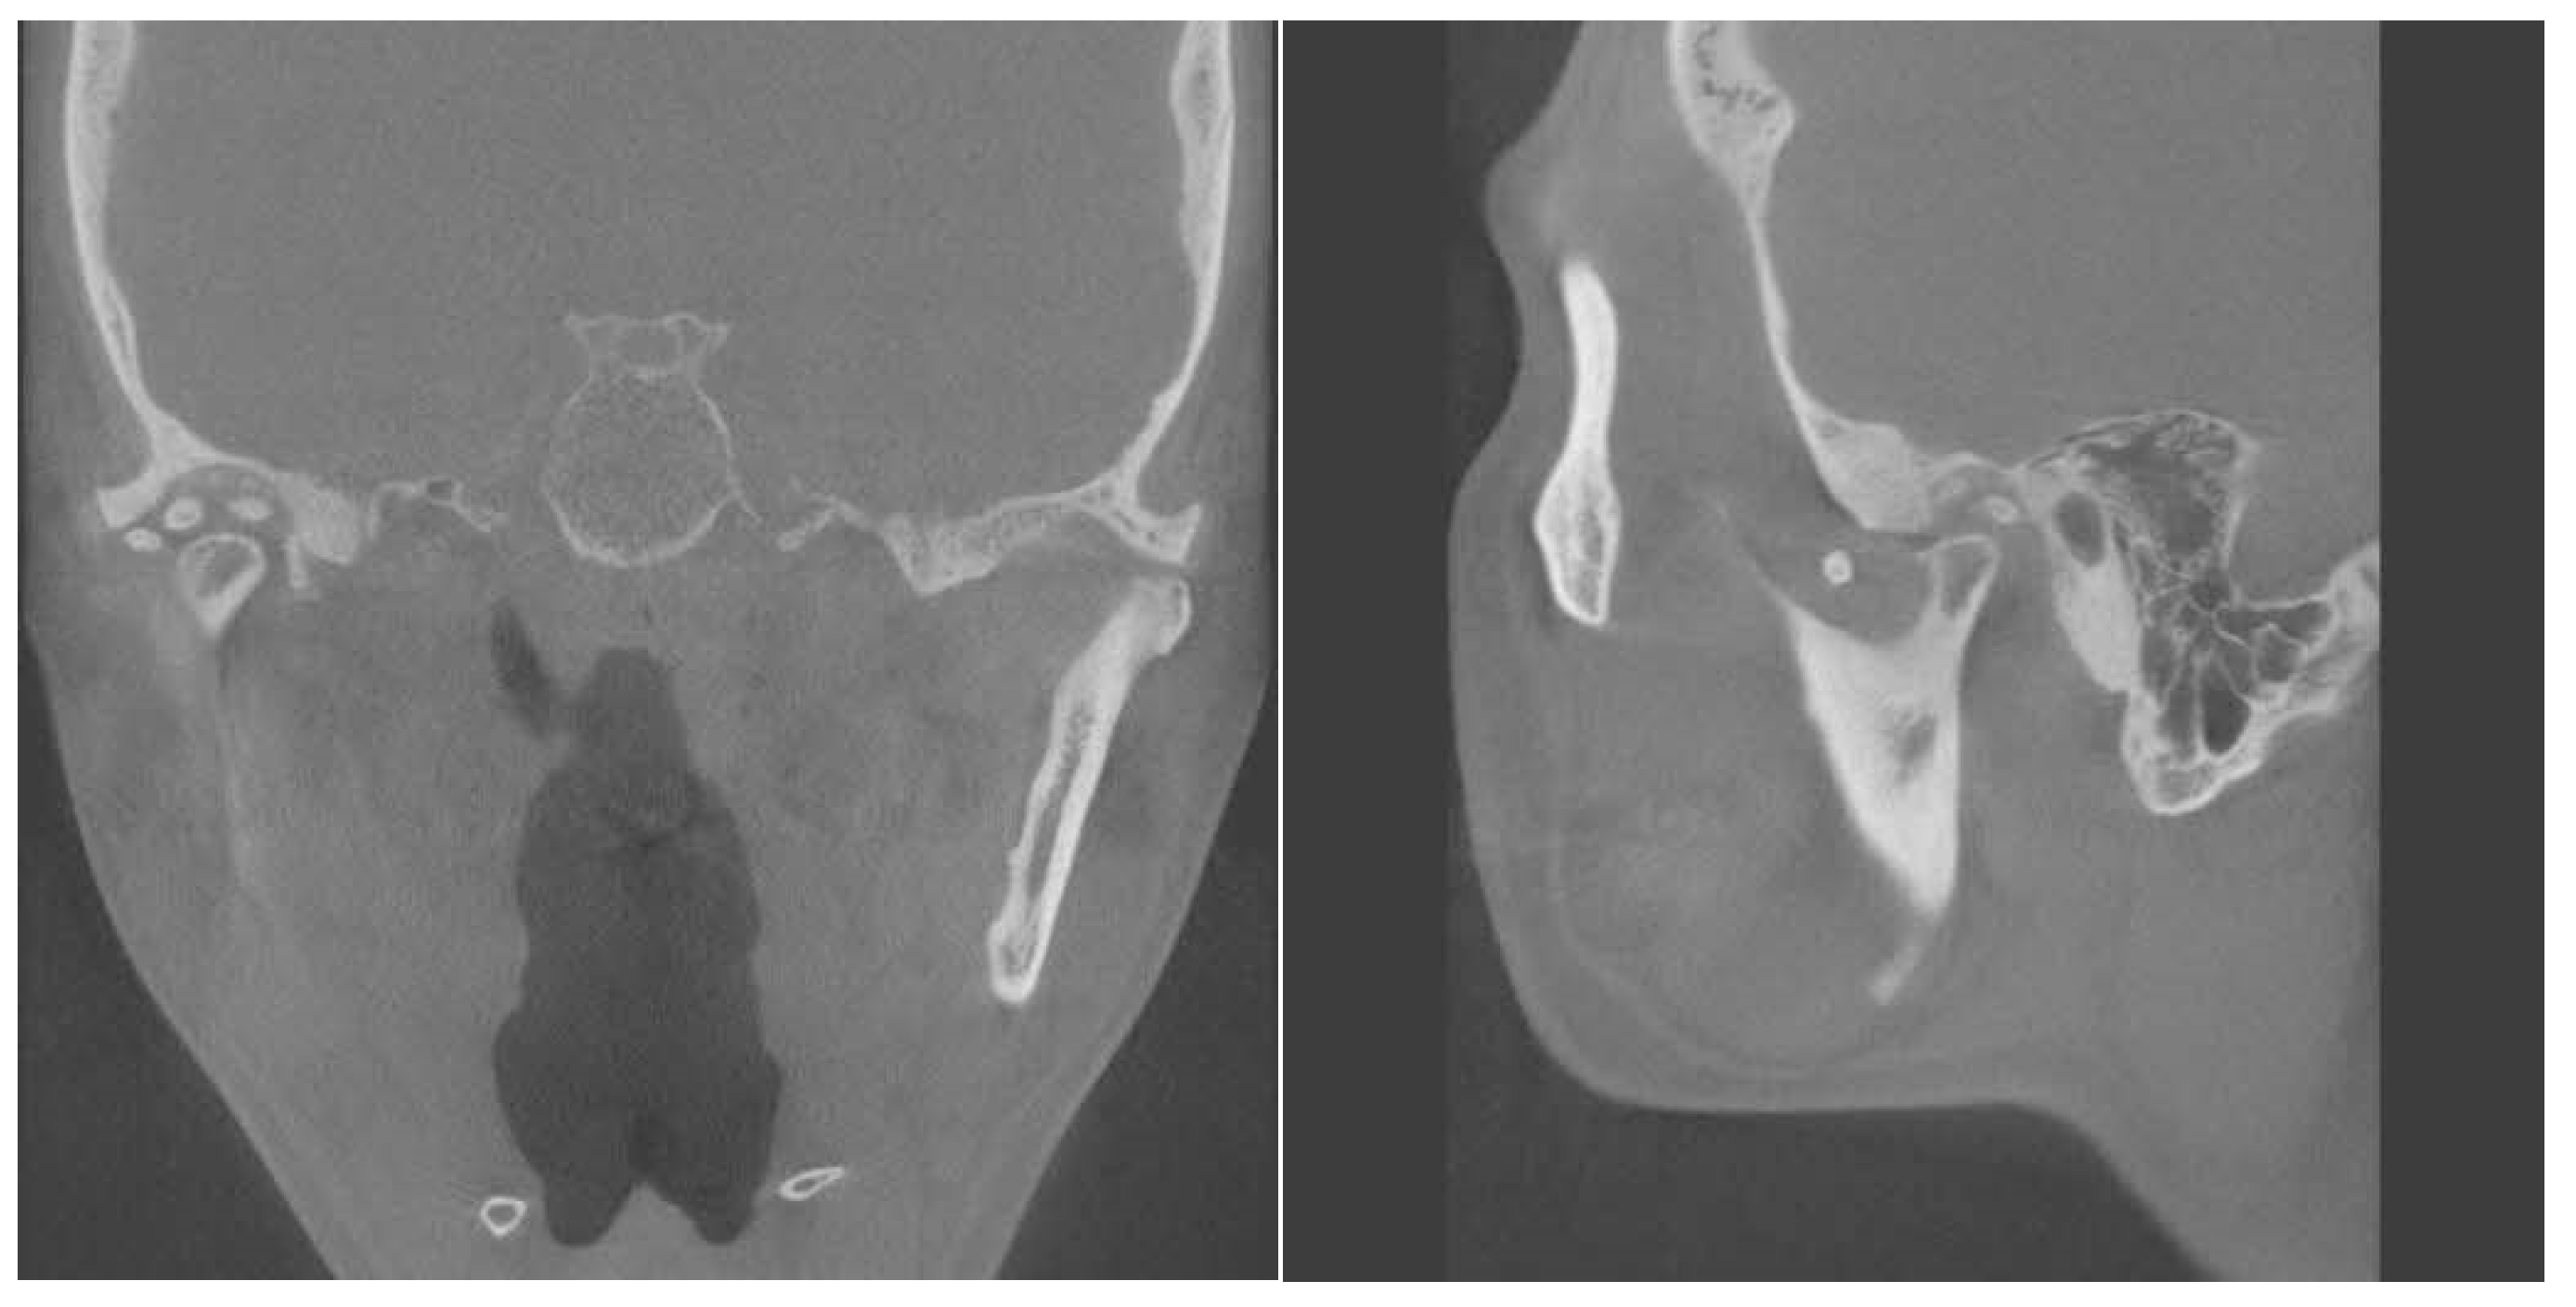

Extensive Synovial Chondromatosis of the Temporomandibular Joint Extending to the Cranial Base